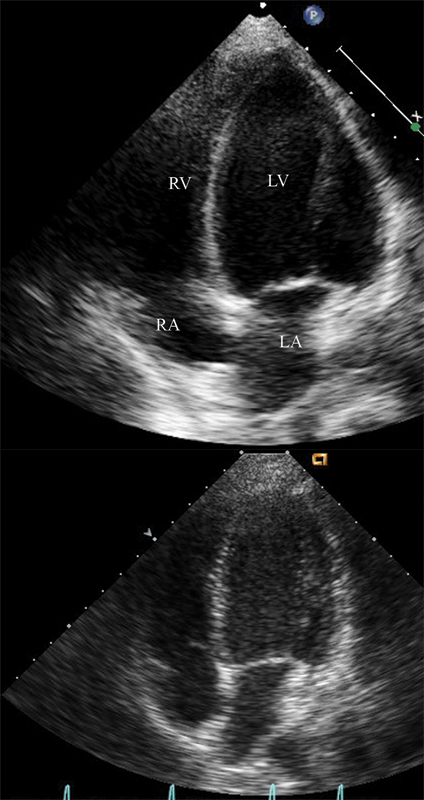

فحوصات تشخيصية لبعض امراض القلب والشرايين التاجية